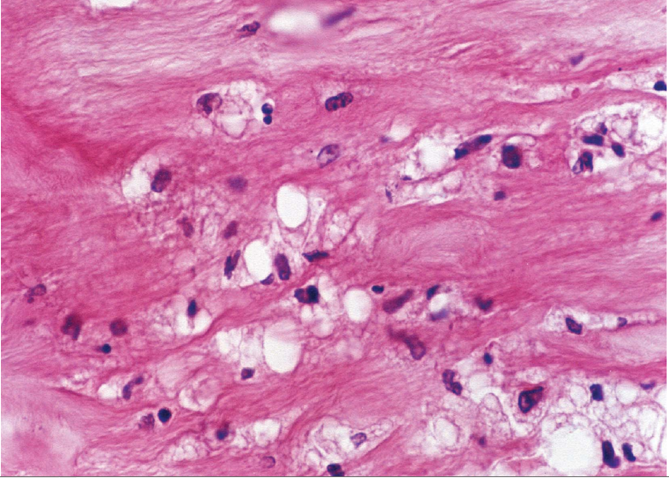

光镜下:脂纹处内皮细胞下有充满脂质的FC(泡沫细胞)大量聚集,FC体积较大,胞浆呈空泡状。FC(泡沫细胞)来源于从血中迁入内膜的单核细胞和由中膜迁入内膜的SMC(平滑肌细胞)吞噬脂质而形成的。此外,可见较多的基质,数量不等的合成型SMC(含大量粗面内质网,核蛋白体及线粒体),少量淋巴细胞,中性粒细胞等。

(图3-3)FC(泡沫细胞)大量聚集,FC体积较大,胞浆呈空泡状。